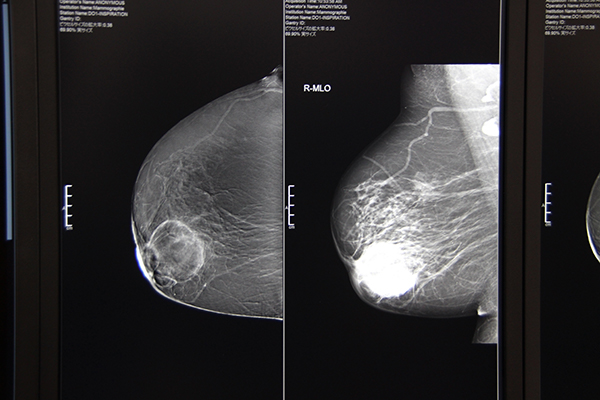

●Women’s Health:多機能化により精密検査を強力にサポートするMAMMOMAT Revelation

Women’s Health エリアでは,ITEM開幕前日の4月12日に発売されたデジタルマンモグラフィシステムMAMMOMAT Revelationの実機と臨床画像を展示した。マンモグラフィシステムはこれまで,精密検査対応の「MAMMOMAT Inspiration」シリーズとスクリーニング対応の「MAMMOMAT Fusion」をラインアップしていたが,MAMMOMAT Revelationはより高度な精密検査のために多機能化が図られている。

Dual Energyとサブトラクション法を使用した造影マンモグラフィ“TiCEM(Titanium Contrast Enhanced Mammography)”を新たに搭載でき,閉所恐怖症などで乳房MRIが受けられない患者に対して造影検査を提供する。造影剤はMRIと異なるため,MRI造影剤にアレルギーがある患者にも造影検査ができる可能性がある。

また,日本人女性に多いデンスブレスト(高濃度乳房)では,マンモグラフィでの検出能が低下することが知られているが,MAMMOMAT Revelationでは通常の撮影と同時に乳腺密度を自動測定する“Insight BD(Insight Breast Density)”を実装することで,客観的な乳腺密度データを表示する。撮影後すぐに,超音波診断装置などによる追加検査が必要かを被検者に説明することができ,より被検者に寄り添った検査を提供できる。

バイオプシーも進化し,ステレオバイオプシーだけでなく,トモシンセシスによるターゲッティングが可能になった。同社のトモシンセシスは±25°と大きな振り角(50°)が特長で,2°ごとに曝射して収集した25枚の2D画像から,トモシンセシス画像を再構成する。この広角撮影により,2D撮影では重なってしまう病変を確実に分離できる。 バイオプシーにおいては,簡単な操作で正確にターゲット設定ができるとともに,“InSpect”機能により患者をポジショニングしたまま採取した標本の撮影が可能で,ワークフロー改善に大きく貢献する。

圧迫板については,乳房圧迫による不快感や痛みを軽減するため,しなりやすい素材を採用した。乳房の形状に沿って全体が均等に圧迫されるため,圧が一点に集中せず,痛みを和らげることができる。また,角に丸みを持たせることで,胸壁や腋窩に接する際の痛みも軽減する。

トモシンセシス撮影では,通常2D,“Insight 2D”(合成2D),“EMPIRE”(逐次近似法を用いたトモシンセシス画像),“Insight 3D”(立体的な情報を提供する回転画像)の4種類の画像処理が行われ,いずれもピクセルサイズ85μmの画像を提供する。

精密検査対応のMAMMOMAT Revelation

MRI検査非適応の患者に造影検査を提供する造影マンモグラフィTiCEM

トモシンセシス撮影で得られる画像(左から通常2D,Insight 2D,EMPIRE,Insight 3D)